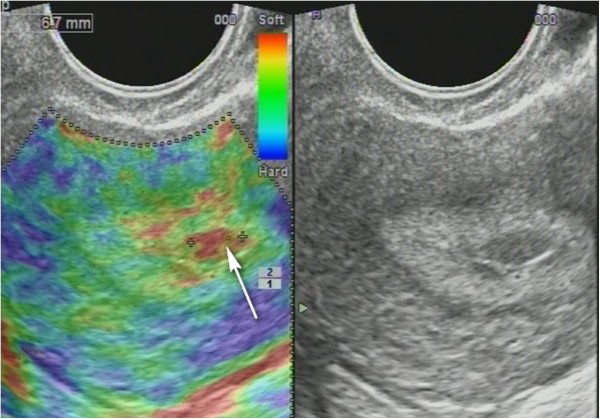

Non-homogenous and irregular margins were significantly higher in AEH than in both groups (P < 0.01). Mean M-echo thickness was found to be non-significant. Hypoechoic areas, hypervascularity on Doppler imaging, and stiffness (Figures 14 and 15) were more specific for AEH than for glandular cystic hyperplasia (P < 0.01, P < 0.01, P < 0.01, respectively; Figure 16). Fluid in the uterine cavity and BGR artefact were found to be specific for AEH (P < 0.01; Figure 17); BGR appearance correlated to the presence of fluid in the uterine cavity (r > 0.97; Figure 18).

Figure 15

Sonoelastography of endometrial lesion. Soft pattern on SEG helps to exclude the polyp.

Figure 16

Glandular cystic hyperplasia that is softer than the myometrium on SEG. E endometrium.